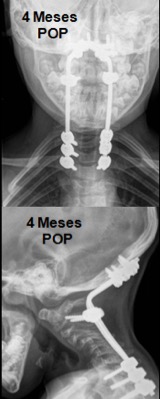

Instrumentación cervical en pacientes menores de 10 años. [Cervical Instrumentation and Fusion in Children Under 10 Years Old.]